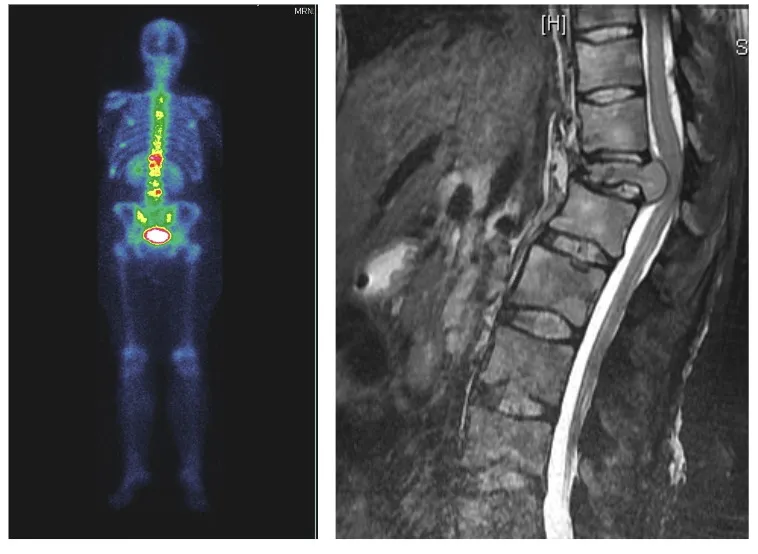

Dolor en cáncer

El dolor oncológico presenta características mixtas, combinando frecuentemente componentes nociceptivos y neuropáticos. La invasión tumoral directa genera dolor nociceptivo por destrucción tisular y liberación de mediadores inflamatorios. La compresión o infiltración de estructuras nerviosas añade un componente neuropático.

Con el aumento de la supervivencia en muchos tipos de cáncer, el control del dolor oncológico se ha convertido en un aspecto crucial de la calidad de vida. Los tratamientos oncológicos (quimioterapia, radioterapia) pueden generar también síndromes dolorosos iatrogénicos, como la neuropatía periférica por quimioterapia o la plexopatía postradioterapia.

El abordaje del dolor oncológico requiere un enfoque multimodal, combinando analgésicos según la escalera de la OMS, técnicas intervencionistas cuando esté indicado, y considerando la expectativa de vida del paciente en la selección de tratamientos.